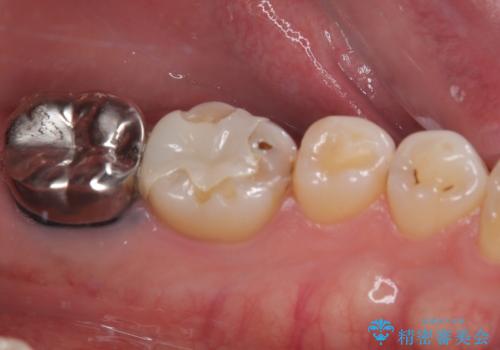

根管治療を行った奥歯は、再発防止や残された歯質を守るため、クラウンによる補綴治療が必要となります。